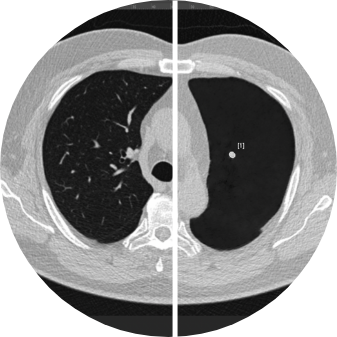

ClearRead CT with Clear Visual Intelligence provides an unimpaired view of the chest for efficient and accurate detection of cardiothoracic diseases. The full suite of tools detects, segments, and measures nodules, compares findings with prior exams, quantifies CAC, and automatically integrates with the radiology report. ClearRead CT is a natural addition for opportunistic CAC and nodule detection or as part of a lung cancer screening program. Detect 29% more nodules and read 36% faster.2,14